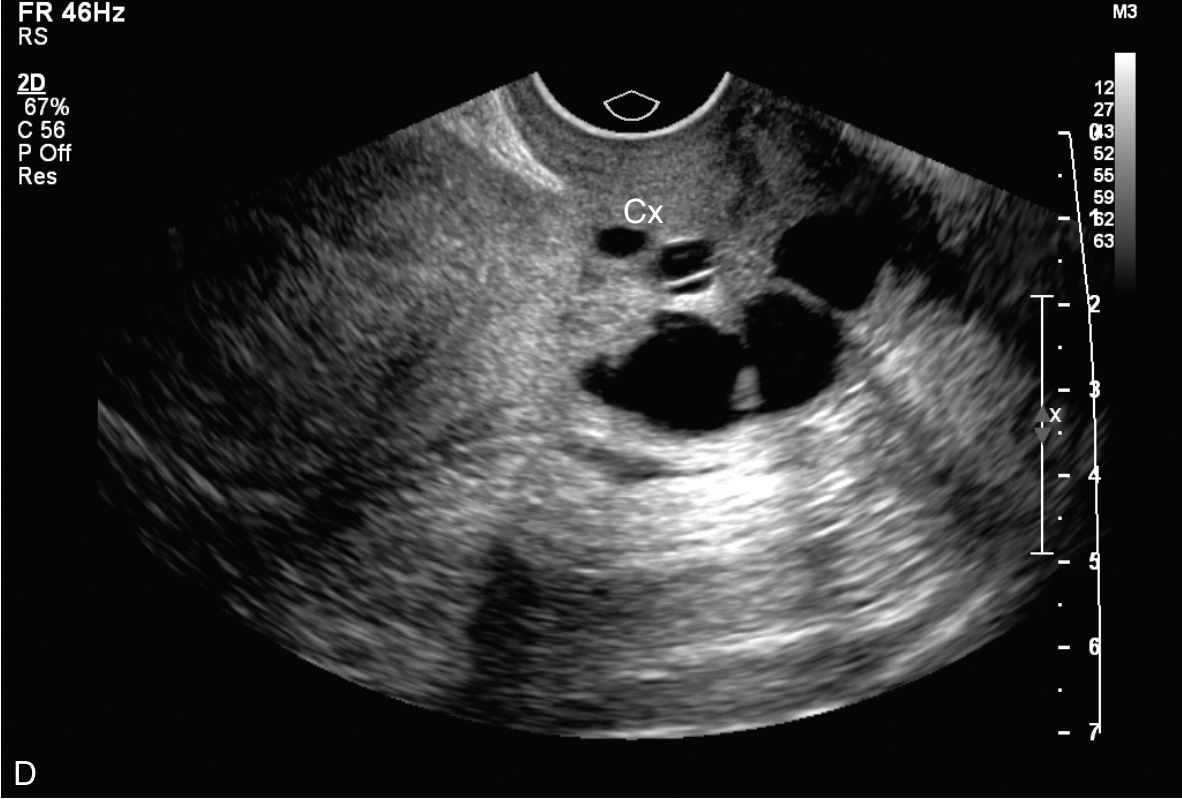

右卵巢上囊肿的经静脉超声造影见图3-12-4及ER 3-12-2。注入造影剂14s,囊肿囊壁开始出现增强(图3-12-4A箭头所示),晚于子宫肌层增强;注入造影剂后18s,囊壁呈较均匀等增强(图3-12-4B箭头所示);注入造影剂后22s,囊肿内始终未见造影剂进入(图3-12-4C箭头所示)。

图3-12-4 右卵巢上囊肿经静脉超声造影声像图

A.注入造影剂后14s;B.注入造影剂后18s;C.注入造影剂后22s。C:囊肿。